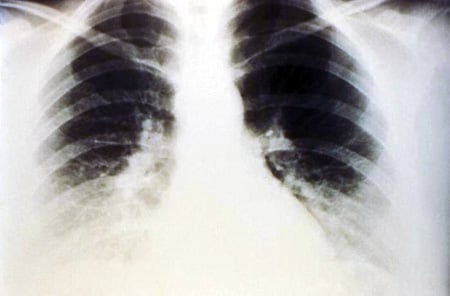

Chest X-ray can detect pleural effusions, as they usually appear as whitish areas at the lung base, and they may occur on only one side (unilateral) or on both sides (bilateral). If a person lies on their side for a few minutes, most pleural effusions will move and layer out along that side of the chest cavity which is positioned downward (because of the effects of gravity). This movement of the pleural effusion can be seen on a chest X-ray taken with the person lying on their side (a lateral decubitus X-ray).